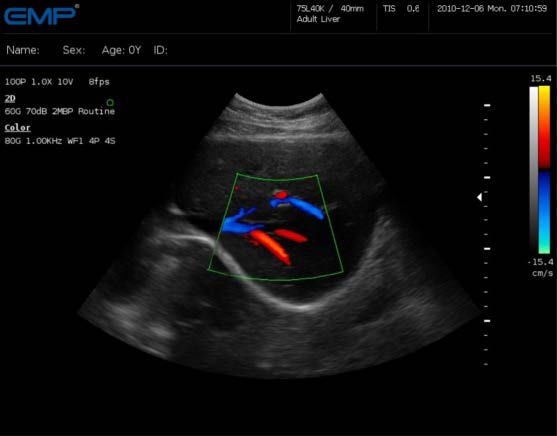

大家可以看到這幅圖的右邊跟左邊相比多了一些紅色和藍色。這就是所謂的“彩超”,它的原理就是“多普勒效應”。運用多普勒效應來探測紅細胞的運動,并將這些運動的方向用彩色表達出來,就形成了彩色血流圖。同時也可以測算出血流速度、阻力指數等參數。為了統一,我們一般將朝向探頭的血流標記為紅色,背離探頭的血流標記為藍色。這個是可以通過檢查者的習慣來調節的并不是一成不變的。

多普勒超聲目前可分為脈沖式多普勒、連續式多普勒、高脈沖重復頻率式多普勒、多點選通式多普勒以及彩色多普勒血流顯像五種,其中脈沖式多普勒應用比較廣。它是在二維超聲心動圖定位情況下,利用多普勒原理,采用一系列電子技術,實時顯示心臟或大血管內某一點一定容積血流的頻譜圖。是一種無創傷性能檢查出心內分流和返流的技術。連續式多普勒可連續發射沖波,因此具有測量高速血流的能力,對于定量分析心血管系統中的狹窄、返流和分流性病變,有其明顯的優點。